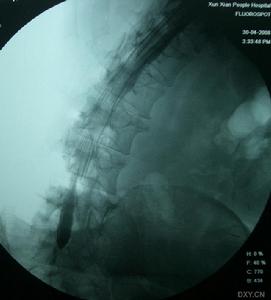

椎管狹窄症正位X線片常顯示腰椎輕度側彎,關節突間關節間距離變小,有退行性改變。側位X線片顯示椎管中央矢狀徑常小,小於15mm就說明有狹窄的可能。必要時可進行腰椎穿刺,奎肯試驗,腦脊液化驗,及脊髓造影。脊髓造影是診斷本症的可靠方法。正位片可清楚顯示硬脊膜腔的大小,如出現有條紋狀或鬚根狀陰影,表示馬尾神經根有受壓現象,或全梗阻,如影柱呈節段性狹窄或中斷,表示為多發性或全梗阻。